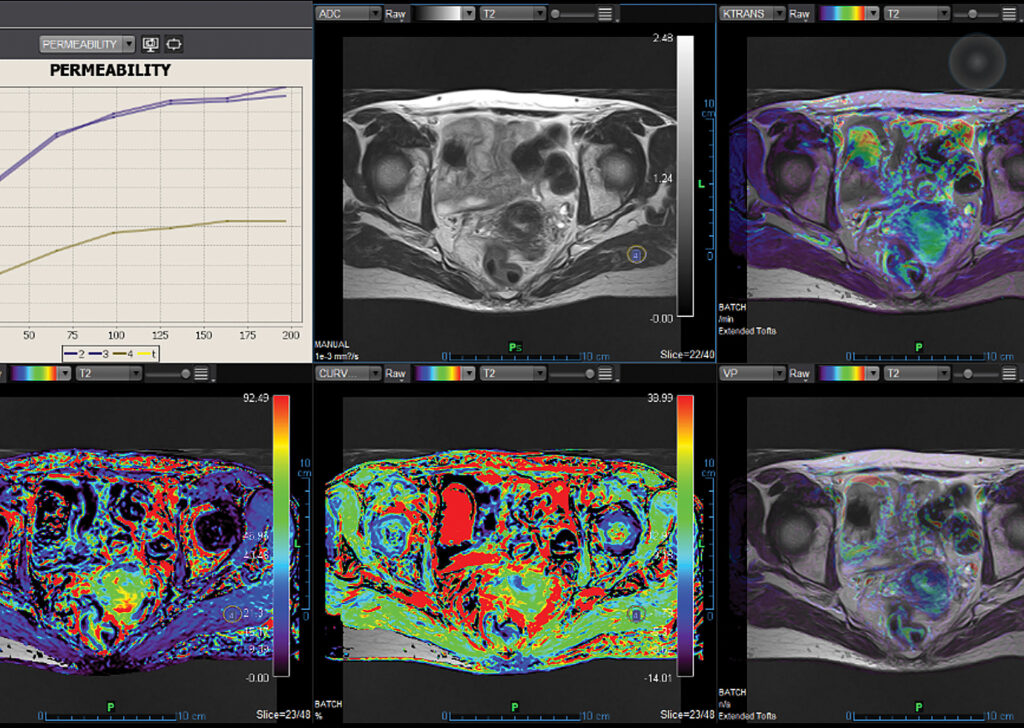

MR Female Pelvis

Olea MR Female Pelvis application is integrated into Vitrea Advanced Visualization and provides efficient analyzation of morphological changes in the pelvic area under pathological conditions.

MR Prostate

Olea MR Prostate application exceeds specialists’ expectations for lesion detection, characterization and staging.